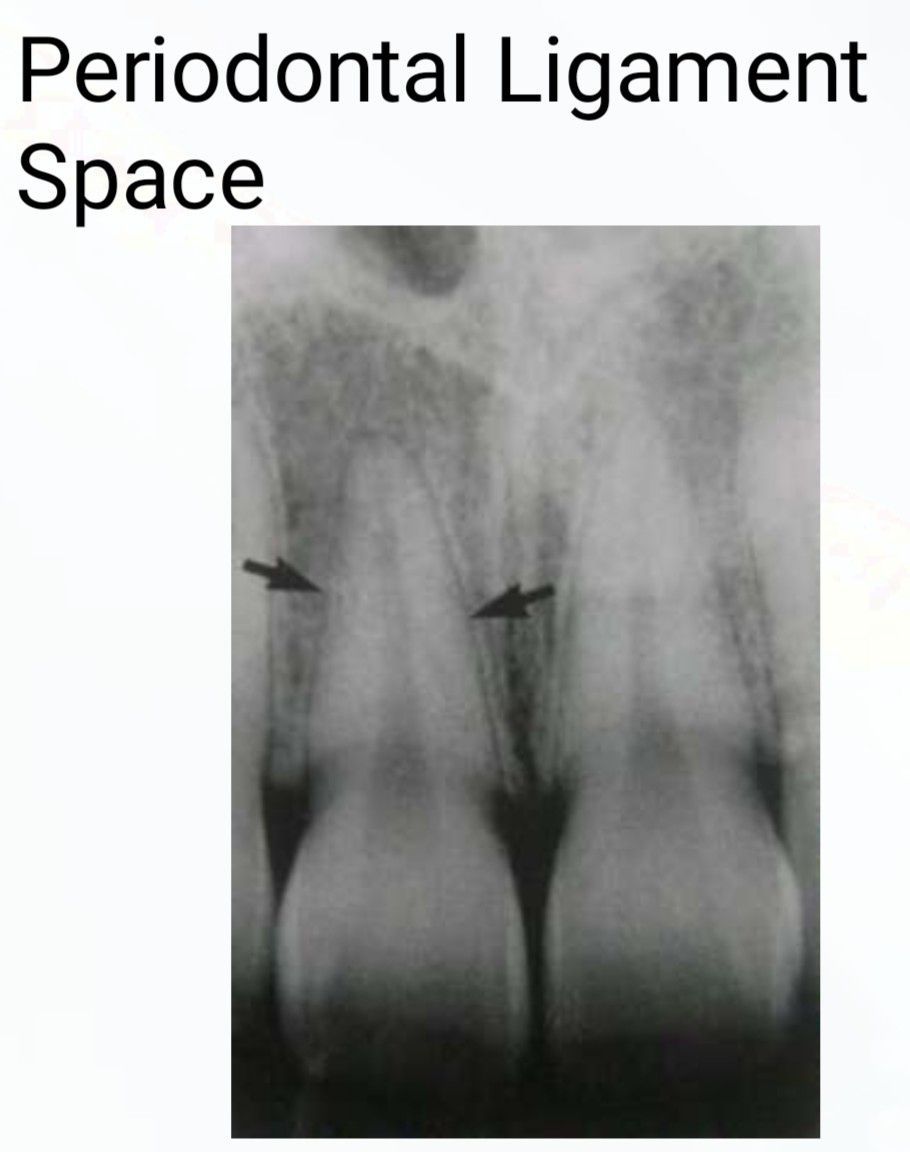

Periodontal Ligament Space

Periodontal ligaments are structures holding teeth in their sockets. They are seen as a thin radiolucent space between the surface of the tooth root and the lamina dura, the lining of the tooth socket.